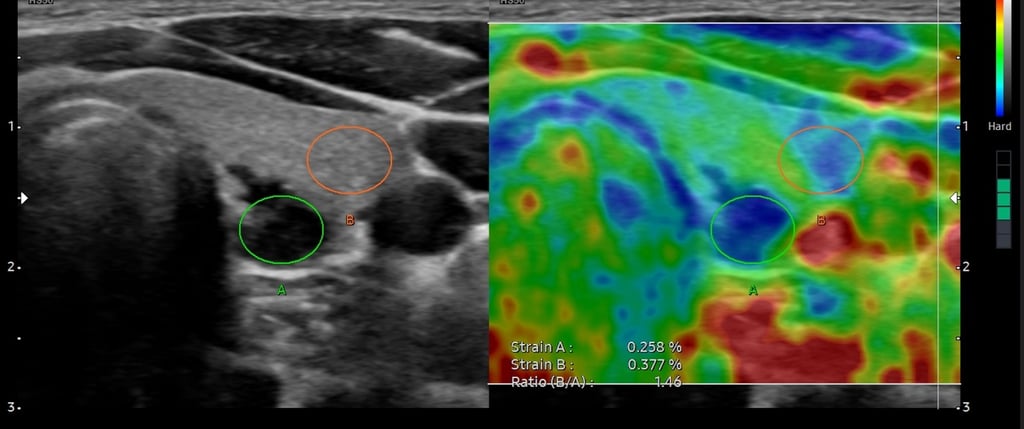

Nodul tiroidian - aspect ecografic sugestiv pentru malignitate - elastografia întărește suspiciunea

BIRADS 5 - tumoră mamară malignă - ecografic hipoecogenă, margini neregulate, halou hiperecogen, rigiditate crescută și SR crescut la elastografie